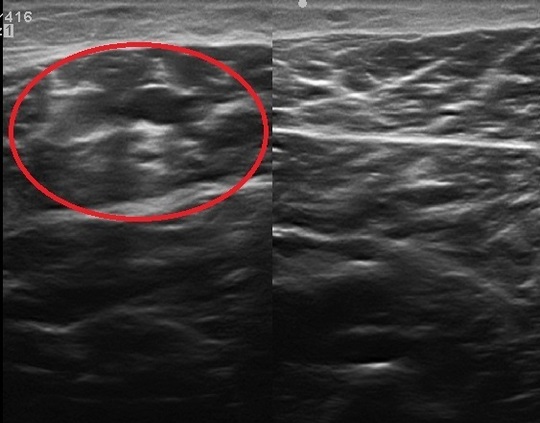

45歳 女性 右ふくらはぎの肉離れ

左:患側

右:正常

1週間前にバレーボールにて足がつったとのこと。そのまま、バレーボールをプレイし、終了直後、痛み増悪。様子を見るも痛み続いているため当院来院。エコー観察にて腫れあり・肉離れと判断。

超音波検査での所見

超音波検査では腓腹筋とヒラメ筋の間に低領域の血腫が観察できる。

レントゲンではわからない筋肉の状態が超音波検査では観察が可能です。

超音波検査では腓腹筋とヒラメ筋の間に血腫を認めます。血腫は時間とともに減少していきます。